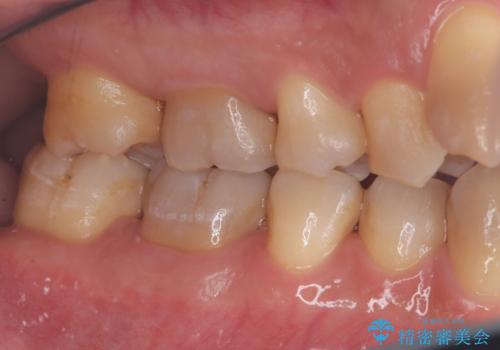

- 学生の頃、前歯をぶつけ歯科を受診したがまだ成長期のため、積極的治療は避けようと言われ十年以上歯科にかかっていなかった患者様です。

前歯は触れると抜けそうで全体的には歯肉の腫れも著しく歯石が沢山ついている状態でした。

歯肉の中にも歯石がついていため細かいスケーリングを何回かに分けて行い、日々の歯磨きのポイントを伝えた所、歯肉の出血や腫れも良くなり、前歯の治療も意欲的に受けられえています。